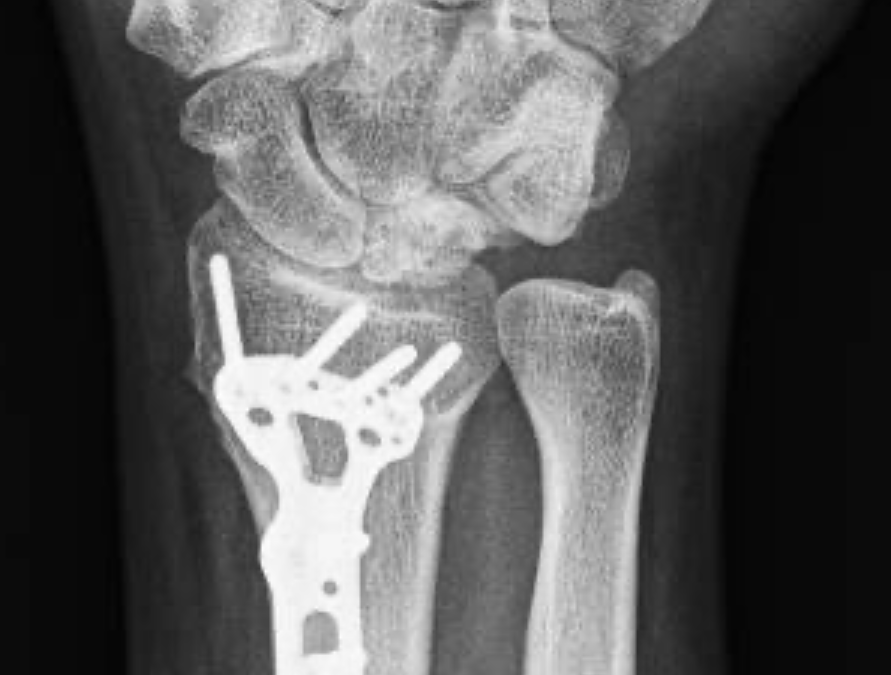

Tratamiento quirúrgico

• Osteotomías (acortamiento o nivelación del radio o el cúbito) para redistribuir las cargas sobre la muñeca.

• Artrodesis parcial o total de la muñeca.